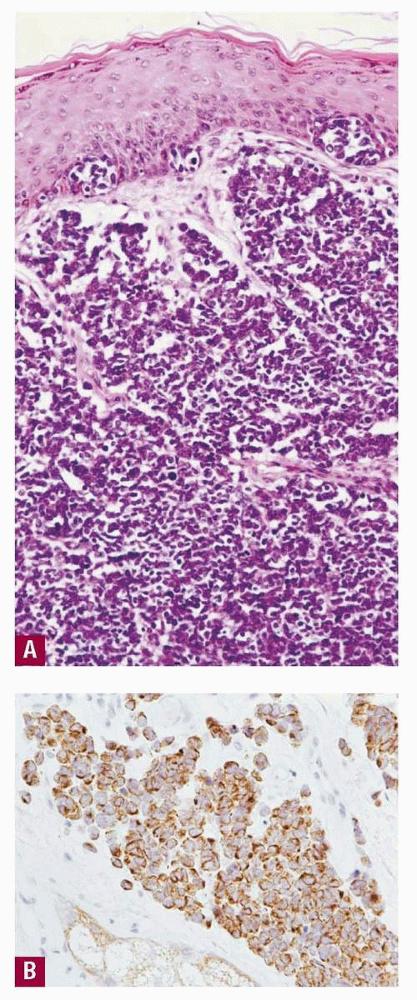

merkel-cell-carcinoma